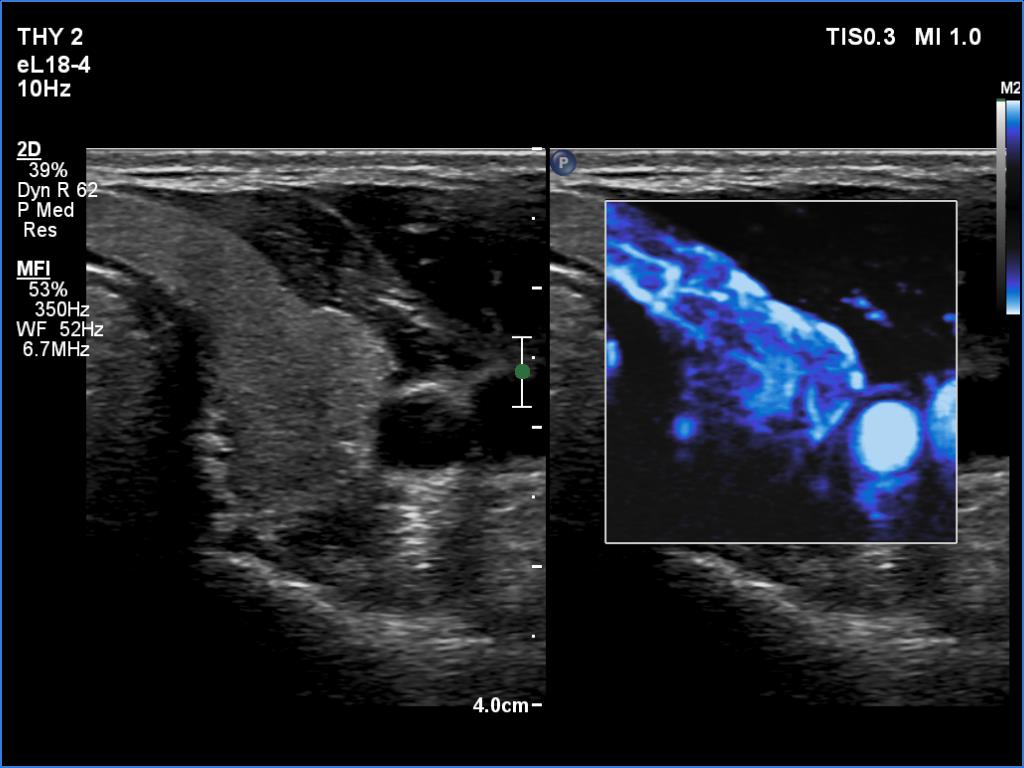

Right lobe, longitudinal scan

Left lobe, transverse scan, microflow imaging. There are more vessels in this lobe than in a usual case.